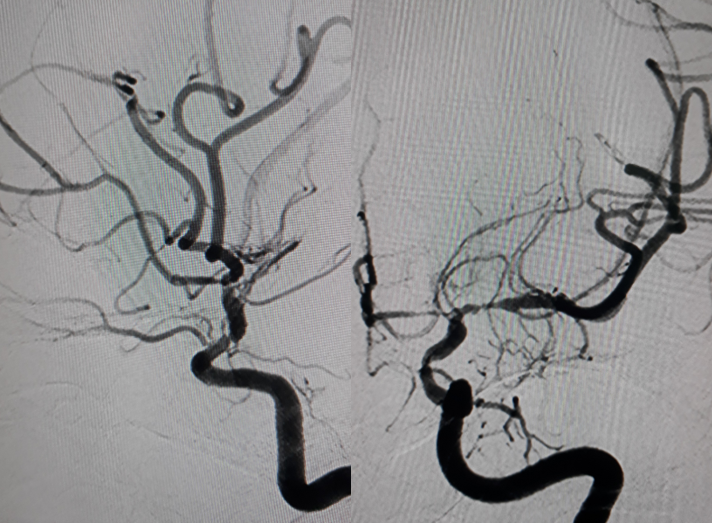

Một bệnh nhân trẻ tuổi, CLVT mạch máu não nghĩ nhiều đến hình ảnh của bệnh Moya Moya, vì vậy bệnh nhân được chỉ định chụp DSA mạch não để khẳng định chẩn đoán đồng thời tiên lượng khả năng điều trị bệnh.

Hình chụp DSA động mạch cảnh trong phải và trái: hẹp khít động mạch não giữa hai bên đoạn M1.

Hình chụp DSA động mạch cảnh trong trái: hẹp khít động mạch cảnh trong trái đoạn mấu giường.

Hình chụp DSA động mạch đốt sống: bàng hệ cho hệ tuần hoàn trước từ hệ thống tuần hoàn sau